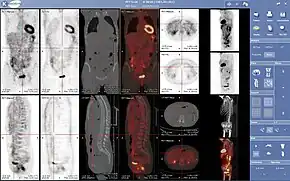

Oncology

PET scanning with the radiotracer [18F]fluorodeoxyglucose (FDG) is widely used in clinical oncology. FDG is a glucose analog that is taken up by glucose-using cells and phosphorylated by hexokinase (whose mitochondrial form is significantly elevated in rapidly growing malignant tumors).[4] Metabolic trapping of the radioactive glucose molecule allows the PET scan to be utilized. The concentrations of imaged FDG tracer indicate tissue metabolic activity as it corresponds to the regional glucose uptake. FDG is used to explore the possibility of cancer spreading to other body sites (cancer metastasis). These FDG PET scans for detecting cancer metastasis are the most common in standard medical care (representing 90% of current scans). The same tracer may also be used for the diagnosis of types of dementia. Less often, other radioactive tracers, usually but not always labelled with fluorine-18 (18F), are used to image the tissue concentration of different kinds of molecules of interest inside the body.

A typical dose of FDG used in an oncological scan has an effective radiation dose of 7.6 mSv.[5] Because the hydroxy group that is replaced by fluorine-18 to generate FDG is required for the next step in glucose metabolism in all cells, no further reactions occur in FDG. Furthermore, most tissues (with the notable exception of liver and kidneys) cannot remove the phosphate added by hexokinase. This means that FDG is trapped in any cell that takes it up until it decays, since phosphorylated sugars, due to their ionic charge, cannot exit from the cell. This results in intense radiolabeling of tissues with high glucose uptake, such as the normal brain, liver, kidneys, and most cancers, which have a higher glucose uptake than most normal tissue due to the Warburg effect. As a result, FDG-PET can be used for diagnosis, staging, and monitoring treatment of cancers, particularly in Hodgkin lymphoma,[6] non-Hodgkin lymphoma,[7] and lung cancer.[8][9][10]

PET scans are increasingly read alongside CT or MRI scans, with the combination (co-registration) giving both anatomic and metabolic information (i.e., what the structure is, and what it is doing biochemically). Because PET imaging is most useful in combination with anatomical imaging, such as CT, modern PET scanners are now available with integrated high-end multi-detector-row CT scanners (PET-CT). Because the two scans can be performed in immediate sequence during the same session, with the patient not changing position between the two types of scans, the two sets of images are more precisely registered, so that areas of abnormality on the PET imaging can be more perfectly correlated with anatomy on the CT images. This is very useful in showing detailed views of moving organs or structures with higher anatomical variation, which is more common outside the brain.